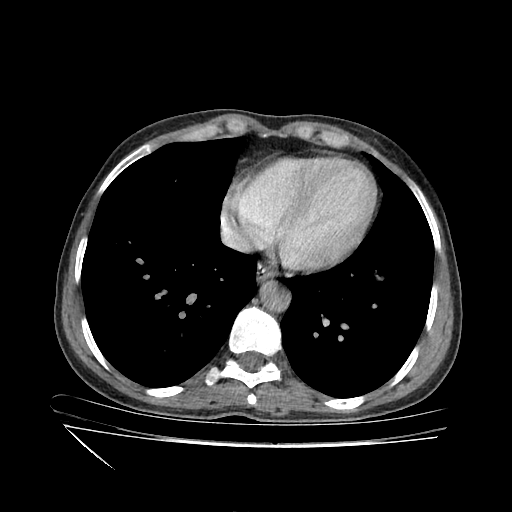

Generated VENOUS CT scan (A→B translation)

Full window (WL 1023.5, WW 4095 β†’ Low βˆ’1024, High +3071)

Actual HU range: [-1024.0, 885.5]